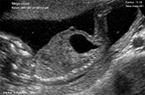

Embryon de 6 SA et jours : cmpositions du sac gestationnel Embryon de 6 SA et jours : cmpositions du sac gestationnel Embryon de 6 SA et jours : cmpositions du sac gestationnel